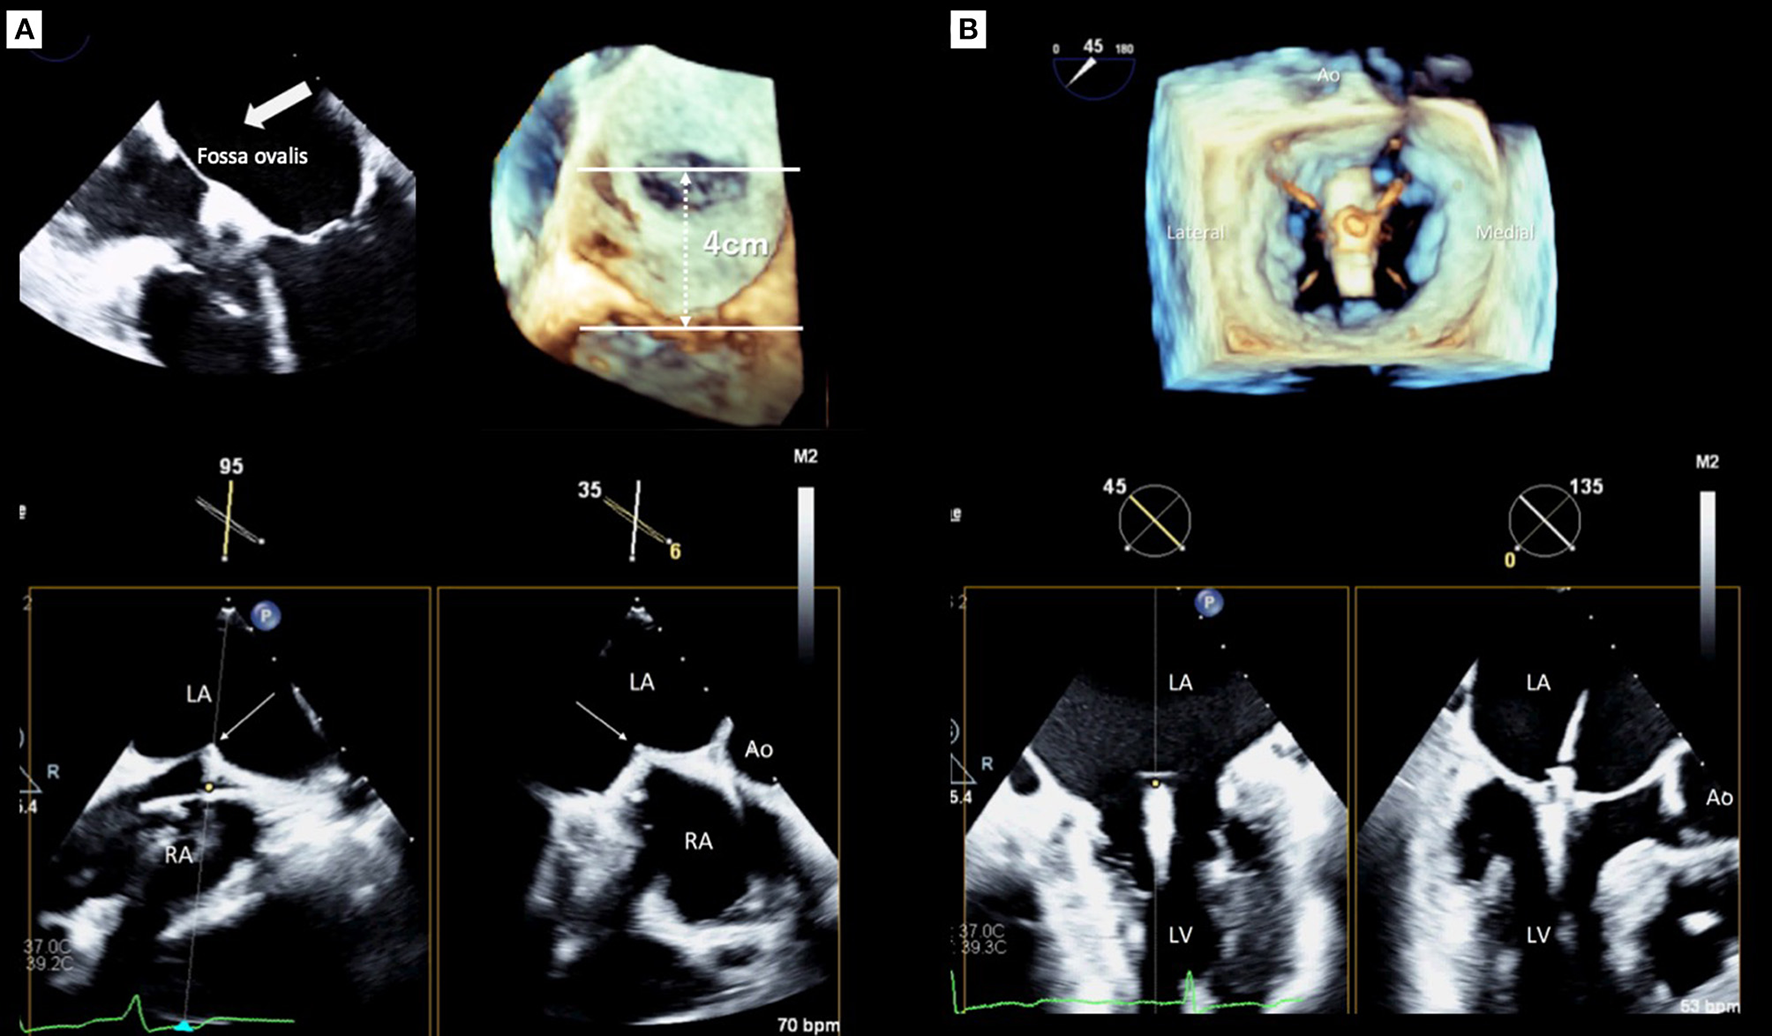

Transseptal Puncture

Determining the optimal transseptal puncture site is an initial crucial role of the 3D TEE guide for TMVr because it fixes the position of the steerable guide catheter (SGC) and influences the mobility of the clip delivery system (CDS) (21). However, clear visualization of the targeted puncture site is sometimes difficult using only 2D images when the site is very posterior (22). Thus, a precise understanding of the interatrial septum and surrounding structures is required for a successful puncture, and the puncture site should be posterosuperior of the interatrial septum. The superior-inferior and the anterior-posterior coordinates of optimal puncture site are commonly confirmed using mid-esophageal bi-caval and short-axis views, respectively. Real-time 3D TEE can provide two planes simultaneously with the x-plane function and will facilitate the identification of the optimal position to be punctured (Figure 2A). However, the ideal puncture site was slightly different between the MR morphologies (23, 24). In patients with primary MR, the height of the puncture site has to be 4–5 cm from the mitral annulus. In contrast, in patients with secondary MR due to leaflet tethering, the height can be reduced because the leaflet coaptation plane shifts to the left ventricle. However, a height from the leaflet coaptation of <3.5 cm should be avoided because it may make the procedure difficult (24, 25).

Figure 2

Real-time guidance for MitraClip implantation using three-dimensional transesophageal echocardiography. (A) Transseptal puncture guidance, (B) Clip deployment. LA, left atrium; LV, left ventricle; Ao, aorta.

Guidance for Clip Deployment

After the CDS was inserted into the left atrium through the SGC, the clip was advanced into the LV. Two orthogonal echocardiographic views are normally used for the procedural guidance; an inter-commissural view and an LV outflow tract (LVOT) view from the mid-esophagus. The X-plane view provides these two planes simultaneously and enables the observation of the device. After the device was advanced to the LV using these X-plane views, the clip was slowly opened. Subsequently, the leaflets were grasped guided by TEE. Real-time 3D en-face MV view helps to assess the alignment of the clip which should be perpendicular to the line of the leaflet coaptation. After an initial grasp of the leaflets, the clip orientation must be evaluated (Figure 2B). Subsequently assessing the adequate insertion of both anterior/posterior leaflets, the MV geometry, which usually has a double-orifice, should be confirmed with the 3D en-face view. Before releasing the clip, the presence of residual MR has to be assessed carefully. Because patients treated with MitraClip had a higher prevalence of cardiac surgery during the first year after the procedure if significant residual MR exists in the EVEREST II trial (26). Moreover, significant residual MR has been shown as a strong determinant of poor outcomes after TMVr in several studies (27–30). Pulmonary venous flow patterns may provide useful information for determining the severity of residual MR indirectly (31). However, quantification of residual MR after MitraClip implantation has been challenging using 2D TEE. The proximal isovelocity surface area method, which is commonly used for evaluating native MR, is not feasible for residual MR after MitraClip implantation since the residual jet may have multiple and eccentric orifices. Color Doppler 3D TEE images help find and visualize the jet if it exists. In addition, 3D VCA may be a feasible and reliable method for quantification of residual MR after TMVr (32). If these results were acceptable, the clip was released. Finally, all evaluations must be performed again to compare the pre- and post-procedural results using both 2D and 3D TEE. If the clip location and the reduction of MR are not appropriate, a new attempt should be made to adjust the clip location.